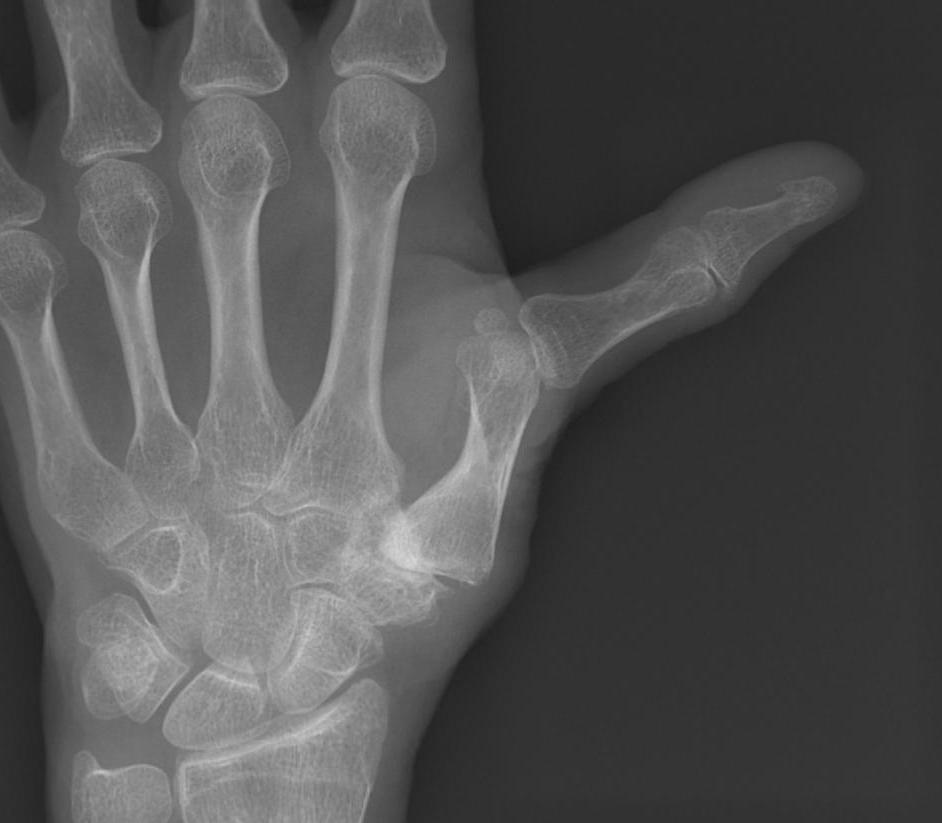

Type IV - Gamekeepers

- due to MCPJ synovitis

- stretches UCL

- either synovectomy / UCL reconstruction

- or fusion